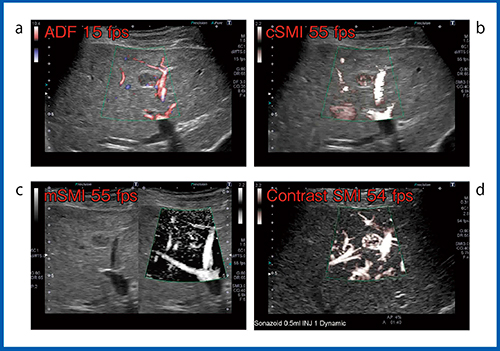

また,図2の膵神経内分泌腫瘍(膵NET)の肝転移症例では,ADF(図2 a)において腫瘍血管の同定が困難であったが,mSMI(図2 c)は腫瘍内に流入する血管の構築が描出できており,多血性腫瘍であることがわかる。ただし,心拍動によるモーションアーチファクトが出ているため造影SMI(図2 d)を行ったところ,非常に鮮明な腫瘍血管像を得ることができた。

図2 造影SMI(d)とADF(a),SMI(b,c)との比較(膵NETの肝転移)